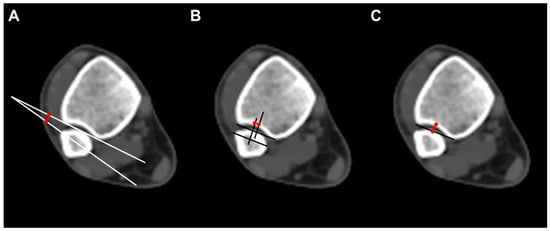

On arrival at NFC, all subjects were screened with bilateral ankle CTs (Aquilion PRIME TSX-303A, CANON Medical Systems Corporation, Tokyo, Japan) (Figure 1A). To provide consistent axial slices parallel to the plafond, the vertical axis of the tibia and the horizontal axis of the plafond were used as reference axes. In addition, the bimalleolar axis, a line perpendicular to the line connecting anterior aspects of the medial and lateral malleoli, was used as a reference to guarantee neutral rotation [,]. For each CT scan, a single axial image 1 cm above the tibial plafond, a level where the length of the distal anterior tibial tubercle is the greatest, was selected for measurement [] (Figure 1B).

Figure 1.

(A) All subjects were screened postmortem computed tomography, (B) A single axial image 1 cm above the tibial plafond, a level where the length of the distal anterior tibial tubercle is the greatest, was selected for measurement.